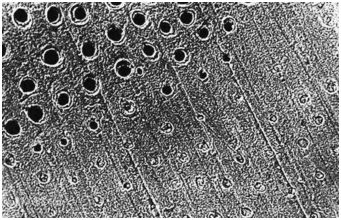

牙本質(zhì)切削后牙本質(zhì)縱斷面,可見牙本質(zhì)小管中存在玷污層栓(放大倍數(shù)2000)